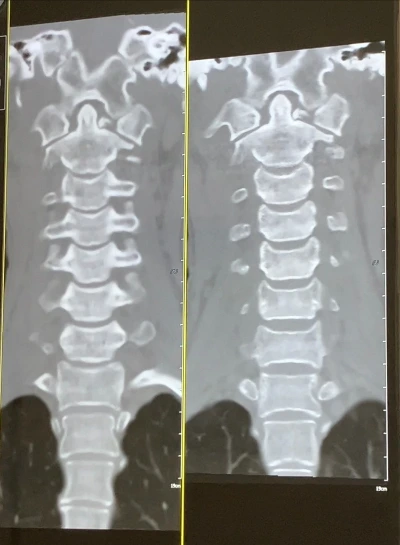

전원한 뒤 첫 CT, 즉 사고가 난 후 찍는

세 번째 CT날이 다가왔다.

한참 CT영상을 들여다보던

교수님께서 운을 떼셨다.

아직 큰 변화는 없네요

여기, 여기 살짝 생길려고 하네요.

브릿지가 생기려고 해요

CT 영상을 한참 들여다보던

교수님께서 뭔가를 발견하신 듯

부서진 경추 1번 부근의

한 지점을 계속 확대해보셨다.

뼈가 붙어가는 과정을

브릿지라고 얘기합니다.

자세한 건 영상의학과 교수님께서 하신

판독지를 봐야 알겠지만

여기 아주 살짝 브릿지가

생기려고 노력중이네요

골절로 갈라져 틈이 생긴 공간에

우리가 보기엔 보일 듯 말 듯 한

아주 희미한 무엇인가가 실타래같이

보이는 듯도 했다.

Still not union, but ongoing osseous union

아직 뼈가 온전히 붙진 않았으나, 골유합이 진행됨.